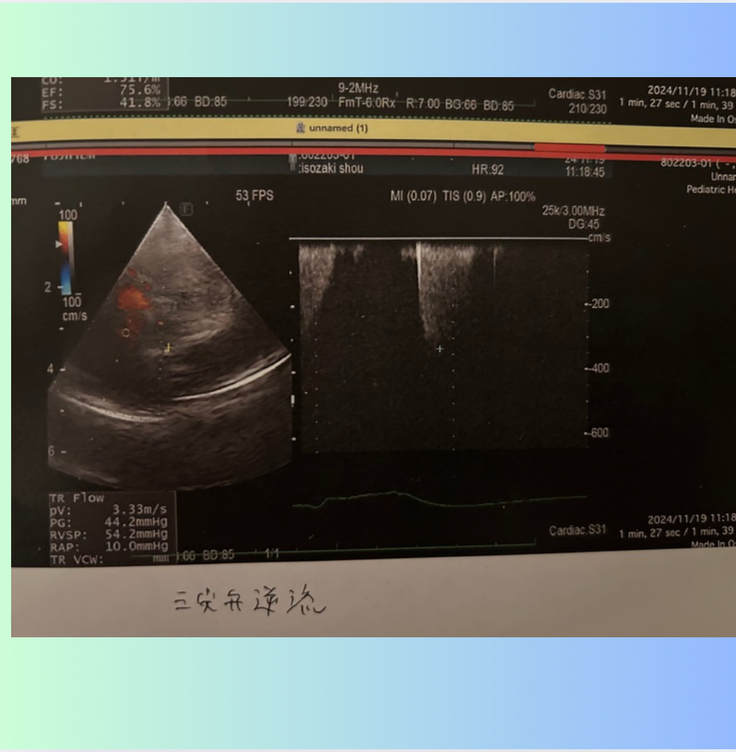

併発がわかった右心側の弁【三尖弁閉鎖不全症】は数値が前回より上がってしまっていました。

前回、少し下がって喜んでいたのですが、また、戻っていました...。

三尖弁の血液の逆流の数値が...

手術前は、 3.9m/s

退院時は、 3.4m/s

1ヶ月検診は、2.6m/s

2ヶ月検診は、3.3m/s